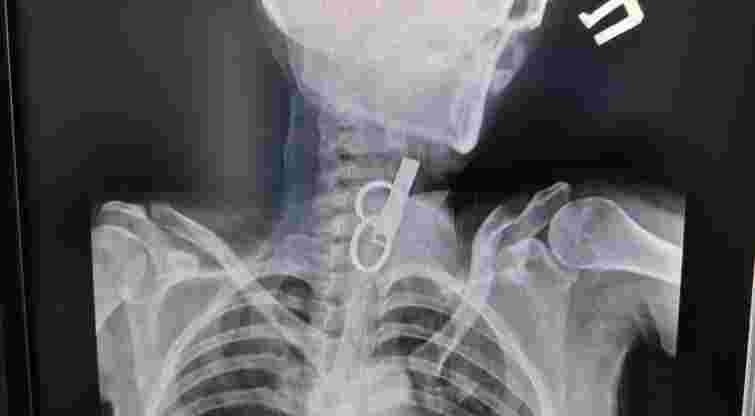

«Це дуже показовий випадок, що нам вдалося її врятувати. Як свідчить практика, переважно такі хворі гинуть. Спочатку ми не могли зрозуміти, що застрягло у стравоході. Це були якісь металеві кільця, які стояли зверху, а далі було ще якесь чужорідне тіло. Я здогадався, що це може бути ключ від дверей і почав його обережно витягувати», – розповів Олександр Садовий.

З’ясувалося, що ключ жінка проковтнула, щоб не віддати його родичам і, щоб вони не мали доступ до її помешкання. Лікар додає, що в обласну лікарню у Тернополі не ризикнули везти пацієнтку, оскільки її вже доставили в стані шоку, то жінку просто б не довезли. Рішення про операцію приймали за лічені хвилини.